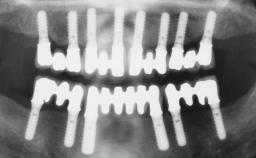

Immediate Implant Placement and Immediate Provisionalization with a Prefabricated-Shell Provisional Crown

In this case, Arndt Happe describes how he achieved a stable outcome at 5 years by giving careful attention to the coronal aspect of the transmucosal area of the provisional, creating a slim emergence profile.

A healthy 31-year-old female patient presented with a failing maxillary left lateral incisor crown. The crown regularly loosened, and the remaining tooth was neither restorable nor rational to treat. The patient had a high smile line, a medium soft tissue biotype with a compromised mesial papilla (shorter than the contralateral one), and a horizontal scar in the buccal soft tissue as a result of past periapical surgery.